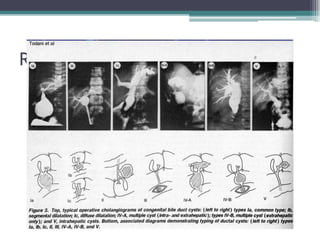

classificationFurther refined in 2003

Classification

• Type I - Cystic or fusiform dilatation of the CBD

• Type II - Diverticulum of the CBD

• Type III - Cystic dilatation limited in intraduodenal

portion of distal CBD

• Type IV - Multiple cystic dilatation of of extra

±intrahepatic bile ducts(IVb)

• Type V - Cystic dilatation of the intrahepatic bile ducts

with normal extrahepatic bile duct (referred

to as Caroli disease)